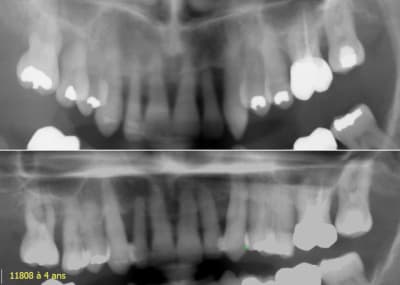

Toujours le même cas, observez la récupération osseuse obtenue, d'abord pendant le traitement puis à 4 ans.

Une ingression, ça change la donne !

Daniel